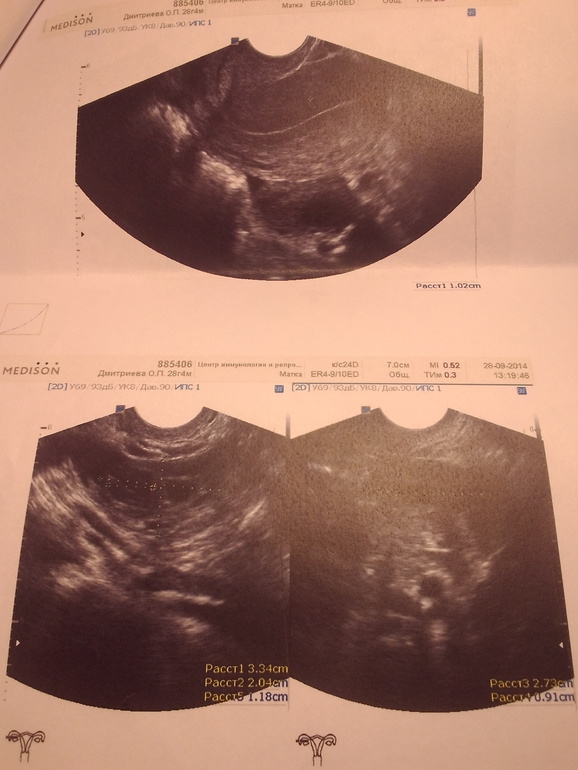

Овуляция( тесты на овуляцию)Девочки, заранее извиняюсь, достала уже всех наверно, но для меня это очень важно!посмотрите картинки с узи!врач пишет, что у меня на 12дц целых 2 желтых тела!не может ли это быть ошибкой?у меня судя по тестам овуляция сегодня- завтра(13-14дц), а по узи получается что все уже было!сейчас нашла в инете инфу, что часто путают жт и дф!

Это левый яичник!

Это правый яичник!

Это верно, что путают ЖТ и ДФ. А жидкость в позадиматочном есть? У меня был фоллик как на первой фотке, казалось, что немного неровные края, но очень тёмный, анэхогенный. Гиня сказала, что это переросток и надо сгонять утрожестаном. А что с Температурой? Хорошо бы через 4-5 дней повторить УЗИ. К сожалению, некоторые вещи только в динамике хорошо смотреть. ЖТ всё время меняется, так что по изменениям можно было бы судить... эндометрий кажется совсем тонким, как в первой фазе сразу после М..

На мой взгляд, это фолликулы, у желтого тела контуры не такие ровные и структура немного другая (по крайней мере на фото моих узи). У Вас в заключении указан размер этих "желтых тел"?

Жт 12мм в ПЯ( Врач говорит наверно с прошлого цикла осталось) и жт 22мм в ЛЯ!А сегодня болит левый бок, выделения весь день как вода и тест на овуляцию почти положительный!

Если жт с прошлого цикла-это уже не жт, а функциональная киста. А вот 22мм- это доминантный фолликул,как я считаю. Мое мнение-сходите еще дня через 3 на УЗИ.